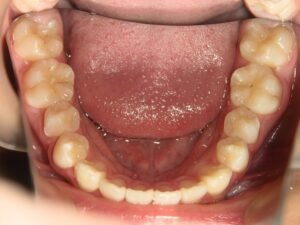

第1期治療終了時

顔貌写真

口腔内写真

治療結果

上の前歯のデコボコが改善

上の歯の狭さが改善

目標の永久歯萌出スペースを確保

第2期治療へ移行

上の前歯の裏側に保定装置(Fixリテーナー)を装着し、全ての永久歯萌出後に全顎矯正を行い、全体的な咬み合わせの調整を行います。

経過観察期間:2年7か月